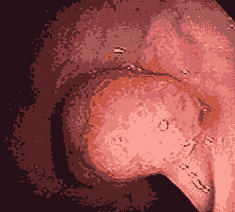

直肠息肉脱出图片

直肠息肉是比较容易发生的肠道疾病,有单发,也有多发,息肉的大小不一,会出现大便出血、排便时肛门疼痛、粘液便等情况。洛阳东大肛肠医院医生提醒:越大的息肉越有癌变风险,建议尽早切除。

脱垂:息肉较大或数量较多时,由于重力的关系牵拉肠粘膜,使其逐渐下垂,可并发直肠脱垂。